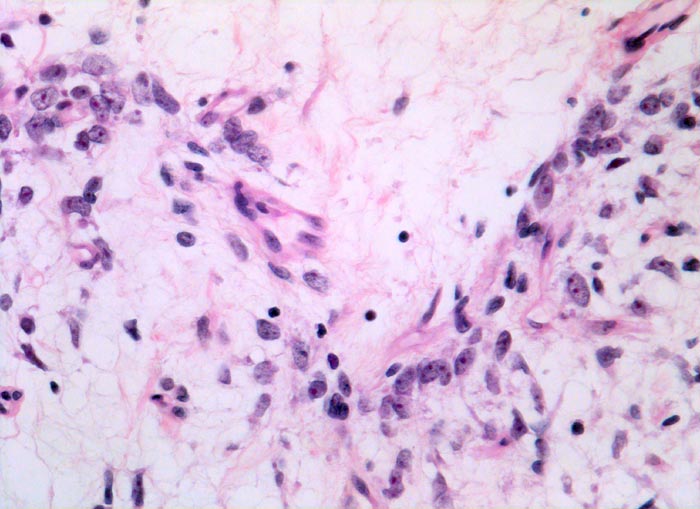

• Am rechten Rand des Präparates komprimierte Skelettmuskulatur.

• Links daran angrenzender scharf begrenzter Tumor mit reichlich myxoidem Stroma.

• Zahlreiche, überwiegend univakuoläre Lipoblasten. Zellkern durch die Lipidvakuole komprimiert und zur Seite verdrängt.

• Zahlreiche krähenfussartig verzweigte Kapillaren.

• Die rundzelligen Anteile erscheinen in der Übersicht aufgrund des Zellreichtums dunkler. Sie bestehen aus dicht gelagerten zytoplasmaarmen Tumorzellen mit vesikulären runden Kernen und einem prominenten Nukleolus.